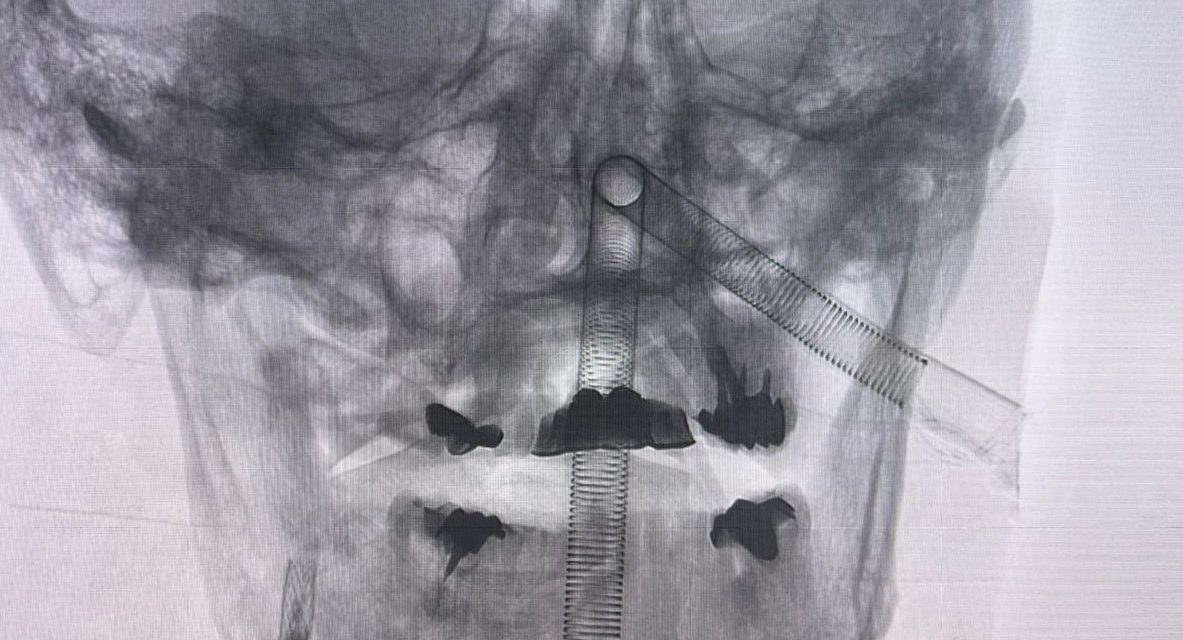

La intervención requirió que se contara no solamente con el block quirúrgico del hospital, sino, además, de la sala híbrida, que es en donde se encuentra el angiógrafo —aparato que, mediante rayos X, permite observar los vasos sanguíneos del organismo, como las arterias y venas—. Allí, los médicos detectaron un coágulo que estaba bloqueando la arteria, por lo que lo retiraron y posteriormente continuaron con la operación en el quirófano. La cirugía resultó exitosa y el paciente ha venido evolucionando satisfactoriamente, sin complicaciones.